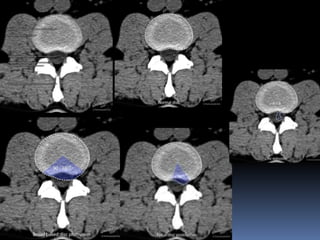

Spinal cord injury

There are two types of injury

to the spinal cord:

Non-hemorrhagic with only

high signal on MR due to

edema.

Hemorrhagic with areas of

low signal intensity within the

area of edema.

Non-hemorrhagic and hemorrhagic spinal cord injury

Spinal cord injury Thereare two types of injury to the spinal cord: Non-hemorrhagic with only high signal on MR due to edema. Hemorrhagic with areas of low signal intensity within the area of edema. Non-hemorrhagic and hemorrhagic spinal cord injury